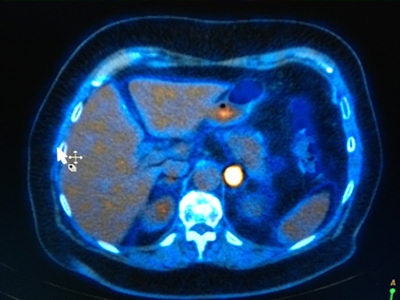

Fowler noted that since x-rays were developed, the vast majority of imaging has been structural and anatomical, but this has shifted to PET/CT and other nuclear medicine technologies. "In the future, this will expand to new techniques such as molecular imaging for targeting specific disease processes such as those involved in inflammatory diseases and cardiovascular diseases, as well as cancers that already use advanced imaging techniques."

In parallel, there will be new ways of dissecting out gene sequences, and it will be essential to become more specific with imaging diagnostics, he added. Currently, MI is mainly used in PET/CT for cancer diagnosis, providing excellent images from which to make a diagnosis and monitor response to treatment. In this era of personalized medicine, having decided that a patient has a subtype of disease, that subtype will be targeted by a variety of investigative agents and MI will evaluate which actually works, he explained.